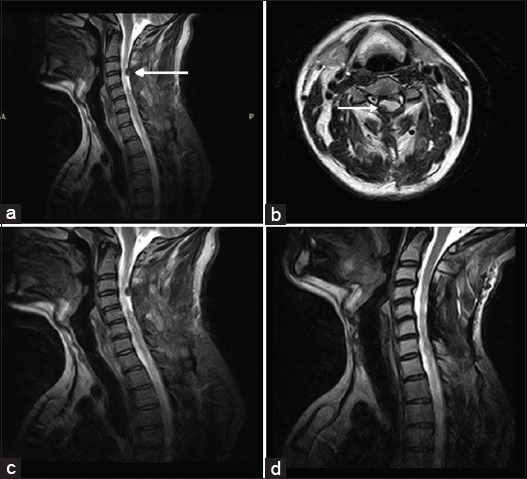

Introduction: Primary spinal malignant melanoma (PSMM) of extramedullary intradural origin is a rare malignant condition with limited current literature regarding its clinical course, magnetic resonance imaging (MRI) findings, treatment strategies, and outcomes.

Case discussion: This is a case report of a patient with PSMM who was treated with surgery followed by radiotherapy for his residual disease in Shaukat Khanum Memorial Trust, Pakistan. The clinical and radiological findings of this case were retrospectively analyzed using the Hospital Information System.

Practical implementations: PSMM of extramedullary intradural origin is a rare malignant tumor that shows characteristic findings on MRI. Surgical resection is the preferred treatment, and radiotherapy is useful for residual disease.